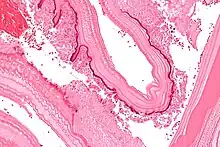

Micrograph showing the characteristic laminated cyst wall.H&E stain.

In the human manifestation of the disease, E. granulosus, E. multilocularis, E. oligarthrus and E. vogeli are localized in the liver (in 75% of cases), the lungs (in 5–15% of cases) and other organs in the body such as the spleen, brain, heart, and kidneys (in 10–20% of cases). In people who are infected with E. granulosus and therefore have cystic echinococcosis, the disease develops as a slow-growing mass in the body. These slow-growing masses, often called cysts, are also found in people that are infected with alveolar and polycystic echinococcosis.[9][10]

The cysts found in those with cystic echinococcosis are usually filled with a clear fluid called hydatid fluid, are spherical, and typically consist of one compartment and are usually only found in one area of the body. While the cysts found in those with alveolar and polycystic echinococcosis are similar to those found in those with cystic echinococcosis, the alveolar and polycystic echinococcosis cysts usually have multiple compartments and have infiltrative as opposed to expansive growth.[11][12]